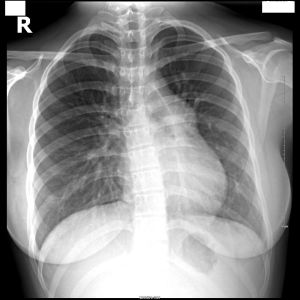

1、胸部X線檢查對肺動脈高壓的判斷有一定幫助,但無一徵象能準確地反映出肺動脈高壓的程度。常用於提示肺動脈高壓的X線徵象有:

①右下肺動脈橫徑增寬,國人正常值小於15mm;

②肺門寬度與1/2胸廓橫徑比增加,即從前正中線至肺動脈段緣間的距離與1/2胸廓橫徑之比,正常值為(28.1±4.5)%;

③肺門胸廓指數增加,即從前正中線水平至左、右肺動脈主要分支間距離之和與整個胸廓橫徑之比,正常值為(34±4)%;

④肺動脈段突出,正常值小於3mm;

⑤肺門動脈擴張與外圍紋理纖細形成鮮明的對比或呈“殘根狀”;

⑥右心房、室擴大;

⑦心胸比率增加,正常小於0.5。需指出,輕、中度原發性肺動脈高壓的胸部X

線可無異常所見,重症患者改變明顯,診斷的敏感性較高。